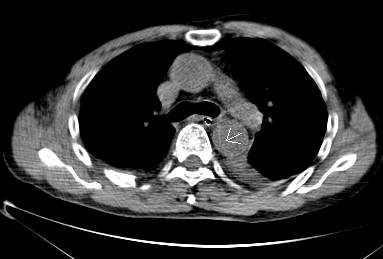

病例六

平扫CT提示降主动脉内膜片影(白箭头所示),CTA显示为B型主动脉夹层。